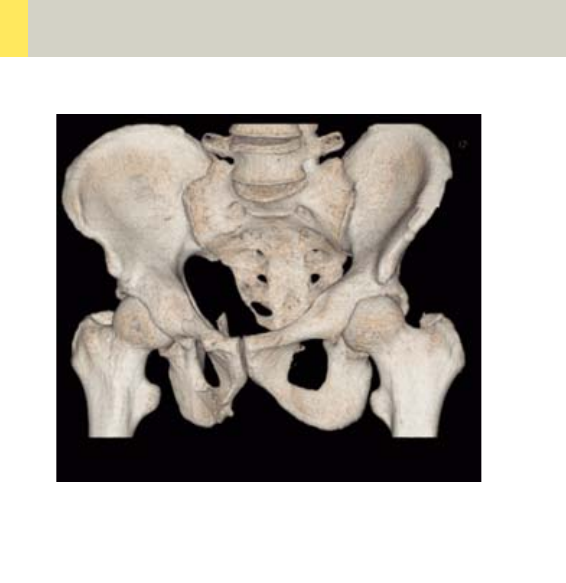

Pelvis 314

•Overview 314

- General Hints 316

- Body Kernels 317

•Scan Protocols 318

- Pelvis 318

- PelvisVol 322

- Hip 324

- HipVol 328

- SI_Joints 330